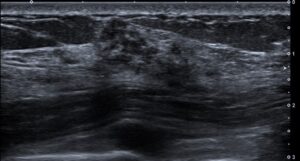

ある日、健診で乳腺超音波検査を行っていた際

気になるエコー像を見つけました。

明らかな腫瘤像は認めませんが

テクスチャーの異なる部分が突出しているように認めます。